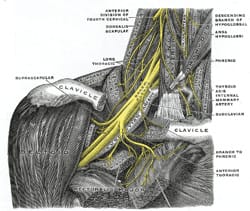

1861

Holmes Coote performed the first TOS surgery. A 26 year-old female servant described a hard mass in her left lower neck, present since childhood. The “tumor” had grown recently, and she experienced paresthesias in the tips of her fingers, with loss of pulses at the wrist, wasting of muscles in the arm, and weakness leading to dropping of items. Mr. Coote explored the area while the patient was “fully under the influence of chloroform.” He noted a bony ‘tumor,’ which he had to divide from the cervical vertebra. He also found it was attached to the first rib anteriorly. He removed as much of the ‘tumor’ as he could, and pulses returned in the left upper extremity. Coote described his trepidation at exploring this area thusly: “But the region was not a pleasant one for any proceeding demanding the use of the knife. The subclavian artery and vein were in front; the axillary plexus of nerves lay spread out above; below, the apex of the lung, covered by the pleura, rose up in dangerous proximity; on the scalenus was the phrenic nerve; while towards the mesial line were the important vessels and nerves passing to the head, together with the vertebral vessels and thoracic duct. You can understand, therefore, why I was cautious in what I did.” The bony tumor was referred to as “an exostotic growth from the transverse process of the seventh cervical vertebra,” and “a development of the costal element, the rib, of the seventh cervical vertebra.” Thus, Coote became the first person to surgically treat a TOS patient.

Mr. Thomas Murphy, of Melbourne, Australia, performs the first resection of a normal first rib for the treatment of neurogenic thoracic outlet syndrome. Thomas Murphy described a 28 year-old woman with symptoms of brachial plexus compression. X-rays showed no cervical rib, but Murphy was convinced the brachial plexus was compressed. Murphy performed surgery, finding the broad insertion of the anterior scalene was compressing the brachial plexus. He removed the insertion and a small part of the first rib. The patient had a “perfect and permanent” recovery.

Thomas Wingate Todd at Manchester University describes the potential causes of neurovascular compression in the thoracic outlet in a series of scientific papers outlining the anatomy and anatomical variations of the thoracic outlet. Dr. Todd’s anatomic dissections included descriptions of cervical ribs, anatomic variations of the first rib and scalene muscles, and the position of the clavicle with shoulder movements. Dr. Todd also postulated that the gradual descent of the shoulder girdle with aging causes narrowing of space between the clavicle and rib, contributing to neurovascular compression. However, Todd also describes in detail a distinct mechanism causing narrowing of only small, distal arteries. In 1912, he shows sympathetic nerve fibers passing from the T2 nerve root to the T1 nerve root variably in humans. In 1913, he demonstrates that pressure on sympathetic nerves causes narrowing and occlusion of small arteries. Dr. Todd became Professor and Chairman of Anatomy at what is now Case Western Reserve University Medical School in Cleveland in 1912. Dr. Todd built the Hamann-Todd Osteological Collection, the world’s largest collection of human and anthropoid skeletons. He also publishes The Atlas of Skeletal Maturation in 1937, and initiated the Brush study in 1926, both of which are widely-accepted tools for the evaluation of human skeletal growth and maturation.

John Sebastian Bach Stopford and E. D. Telford at Manchester University Medical School describe compression of the lower trunk of the brachial plexus by a normal first rib, and report results from 10 patients following resection of the first rib. Stopford and Telford considered the following three key elements as the underlying etiologic factors in development of brachial plexus compression:

Stopford and Telford describe a new mechanism of arterial occlusion caused by nerve pressure in the thoracic outlet, without involvement of the subclavian artery. They describe three patients with severe arterial occlusion and distal gangrene of the fingers and hand. Each of these patients had a cervical rib, but no subclavian artery compression or aneurysm. And, in each patient, removal of the cervical rib provides complete relief of symptoms. Specifically, Stopford and Telford explain how sympathetic fibers of the lower brachial plexus regulate the small arteries of the arm and hand. Considering prior work by Wingate, they demonstrate how some patients have variable anatomy of these fibers, immediately adjacent to the first rib. Thus, pressure by the first rib, or a cervical rib, in some patients causes abnormal regulation of the small arteries. As a result, these arteries constrict over a long period of time. At first, the patients experience pallor and coldness from loss of arterial blood flow. Over time, the lining of the arteries expands, blocking arterial flow. This results in gangrene, or loss of tissue.

1943

David Roos